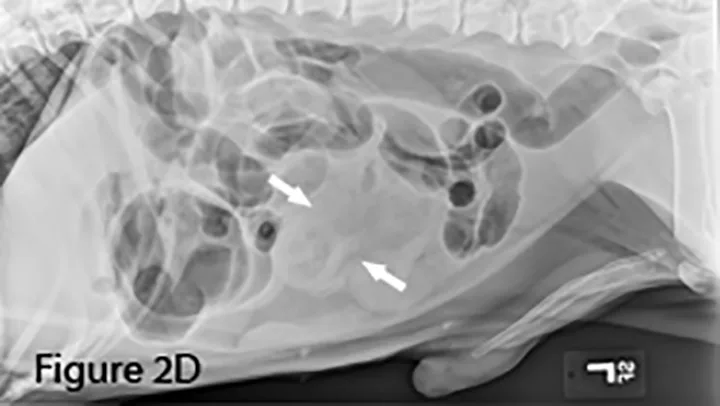

A foreign body (ie, rock) is identifiable in this canine small intestine. The markedly dilated segment of jejunum (arrows) leading up to the foreign body (~4× the height of L5) is significant.